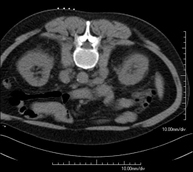

Prova diagnòstica que consisteix en l'estudi de l'abdomen d'alta definició anatòmica (fetge, vesícula biliar, via biliar, pàncrees, melsa, estómac, intestins, ronyons, estructures vasculars, bufeta, úter i ovaris, etc.) mitjançant l'ús d'un equip de TC (Tomografia Computeritzada). Aquestes imatges s'estudien posteriorment en una estació de treball que permet obtenir reconstruccions bidimensionals en diferents plànols de l'espai i també reconstruccions 3D (volumètriques). La majoria d'estudis requereixen l'ús de contrast iodat per millorar la definició de les imatges. - TC Pelvis

Prova diagnòstica que consisteix en obtenir imatges bi i tridimensionals de l'abdomen d'alta definició anatòmica (estructures òssies, estructures vasculars, fetge, pàncrees, vesícula biliar, ronyons, glàndules suprarenals, melsa, intestí prim i gros, bufeta, úter i ovaris, pròstata i vesícules seminals, urèters, etc.) mitjançant l'ús d'un equip de TC (Tomografia Computeritzada). La majoria d'estudis requereixen l'ús de contrast iodat. - TC Fetge